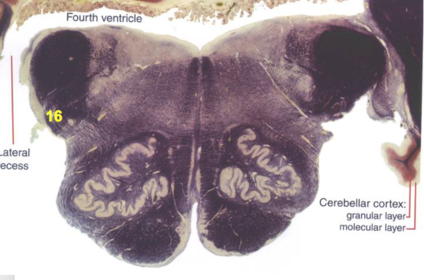

| Superior cerebellar peduncle | |

| Dentate nucleus | |

| Fastigial nucleus | |

| Anterior spinocerebellar tract | |

| Spinal nucleus of V | |

| Spinal tract of V | |

| Middle cerebellar peduncle | |

| Superior vestibular nucleus | |

| Medial lemniscus | |

| Trapezoid body | |

| Ventral trigeminothalamic tract | |

| Superior olive | |

| Longitudinal pontine fibers (corticospinal tract) | |

| Transverse pontine fibers (dark fibers) | |

| Pontine nuclei (pale) | |

| Central tegmental tract | |

| ALS | |

| Medial longitudinal fasciculus | |

| Principle nucleus of V | |

| Mesencephalic V tract | |

| Trigeminal root fibers | |

| Motor nucleus of V | |

| Cerebellar vermis | |

| Lateral lemniscus | |

| Longitudinal pontine fibers (c-spinal, c-bulbar, c-pontine fibers) | |

| Transverse pontine fibers (dark) | |